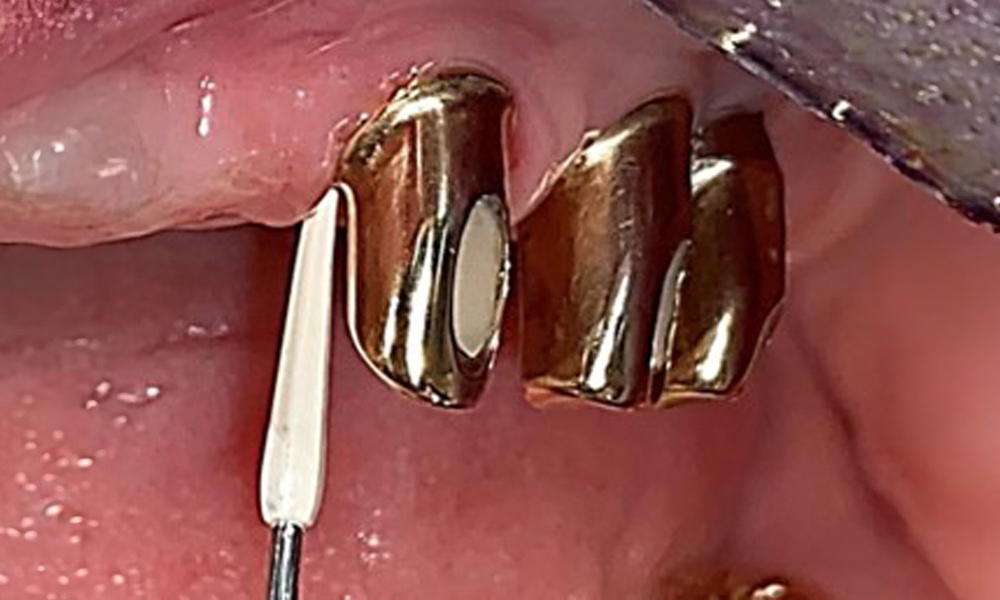

Probing implant 23 at a probing depth of 4 mm using a plastic probe, showing negative BOP findings and a hyperplastic papilla.

Fig. 6: Probing implant 23 at a probing depth of 4 mm using a plastic probe, showing negative BOP findings and a hyperplastic papilla.

The periodontal status should be thoroughly examined once a year. This examination provides comprehensive documentation of the periodontal and implant findings, including pocket depths, periodontal recession and furcation involvement. This will ensure a rapid response to any potential progression of the mucositis, gingivitis, periodontitis or peri-implantitis. Implant probing using a plastic probe is recommended. In the present case, a mesial probing depth of 4 mm was detected mesial to implant 23. No suppuration or bleeding was detected, indicating the absence of peri-implantitis.

Based on the medical history, the risk of complications is classified as mild to moderate due to the intake of ASA 100 and bisoprolol. It should be noted that increased bleeding may occur during treatment, particularly if gingivitis is present. The risk is classified as low in the present case, as the patient maintains excellent intraoral hygiene. Due to the otherwise stable intraoral status over many years, the needs determined during the intraoral examination will be decisive for her treatment. The findings observed during any dental appointment will determine the subsequent course of treatment. Determination of bleeding status is mandatory to detect gingival changes in peri-implant tissues (Fig. 6).